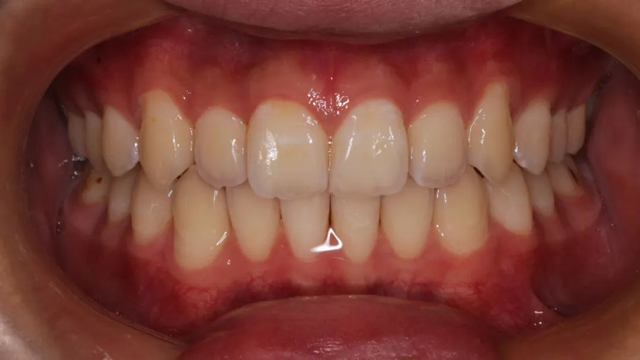

2024年9月(矯正結束后口內照)

“隱形矯正一般2-3月復診一次,從節約時間來說很受家長青睞,但前提是小朋友要有很好的依從性,這是獲得滿意效果的前提。案例中的這個小朋友和家長與醫生的配合度非常高,這也是我們能治療成功的必要因素。”